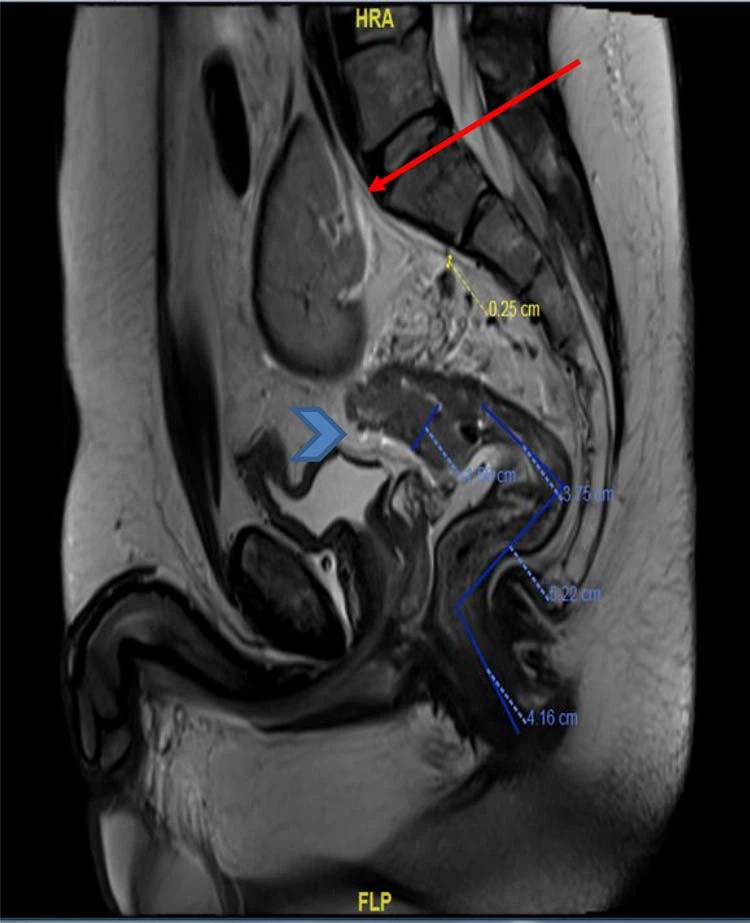

Figura 3.MRI pelvi (dehra sagittali) wera massa tar-rektum ta 'fuq b'involviment ta' xaħam mesorektal (arrowhead) u kliewi pelvika ektopika (vleġġa).

Raġel ta' 40-sena, trux u mut ippreżenta 4 xhur storja ta' fsada għal kull rektum assoċjat ma' bidla fil-movimenti tal-musrana, u ma kien hemm l-ebda uġigħ addominali, l-ebda storja ta' telf ta' piż, u l-ebda storja familjari ta'kanċer tal-kolorektum, l-ebda l-istorja tal-użu tat-tabakk. Fuq valutazzjoni klinika, deher pallidu b'sinjali vitali normali u l-eżami tiegħu wera addome artab, l-ebda sensittività jew mases palpabbli għal kull eżami tar-rektum żvela demm iżda l-ebda tumur palpabbli. L-investigazzjoni bażika tal-laboratorju wriet Hgblevel ta '8.6g/dL. u l-livell ta' CEA ta' 4.8 ng/ml. Fuq investigazzjoni ulterjuri, kolonoskopija żvelat massa rettali ċirkonferenzjali fungating kbira frijabbli f'9 ċm mill-ponta anali li testendi sal-kolon sigmoid distali, ma kinitx tfixkel b'tul ta '8 ċm u l-bqija tal-kolon kien normali. Bijopsija mill-massa ttieħdet u wriet adenokarċinoma moderatament differenzjata. F'rutina ulterjuri ta' stadju radjoloġiku, CT tas-sider, addome, u pelvi kkonfermat il-massa tar-rektum ta' fuq b'kliewi tax-xellug ektopiku malrotat li jinsab fl-addome t'isfel u l-pelvi ta 'fuq, oppost għal korpi vertebrali L5-S1 (Figuri 1 u 2). Ma kien hemm l-ebda mard peritoneali jew metastasi mill-bogħod. Barra minn hekk, il-pelvi MRI wera għal darb'oħra massa tar-rektum ta 'fuq b'invażjoni ta' xaħam mesorectal u lymph nodes multipli (T3N2) u kkonferma kilwa xellugija ektopika (Figuri 3 u 4).